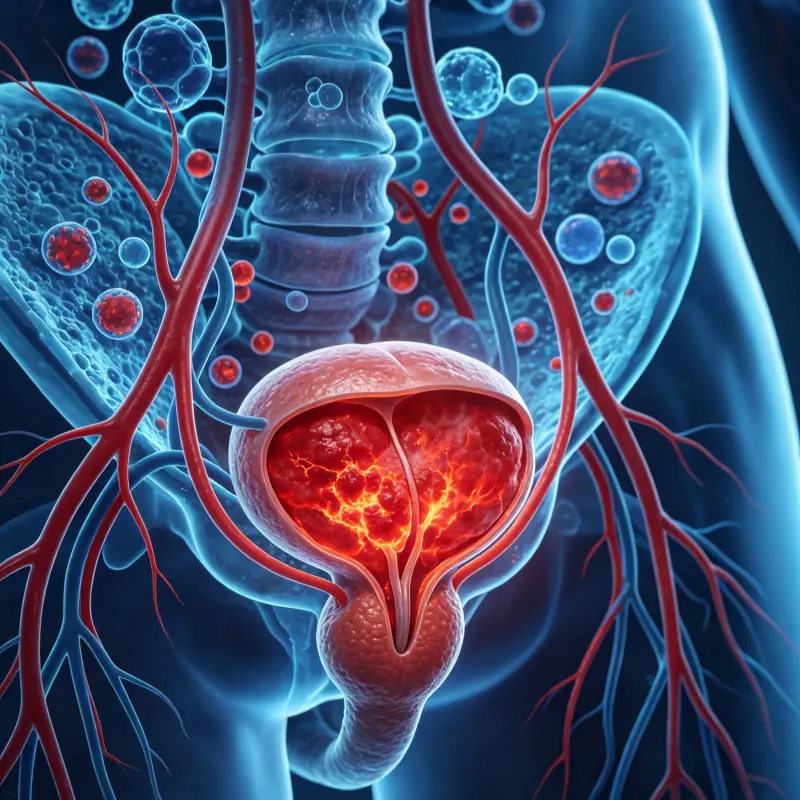

7.感染與炎癥

感染會直接影響精子生成與運動能力。

常見疾病:

前列腺炎

附睪炎

性傳播疾病(如淋病、衣原體感染)

臨床觀察:

慢性炎癥會導致精子活力下降,並增加畸形率。

前列腺炎